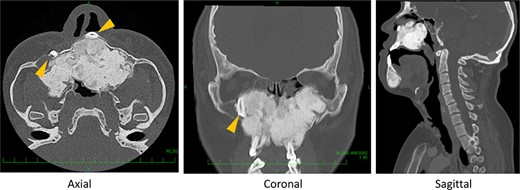

Post-operative CT midline bone has been drilled out, and space for nasal airflow has been widened.